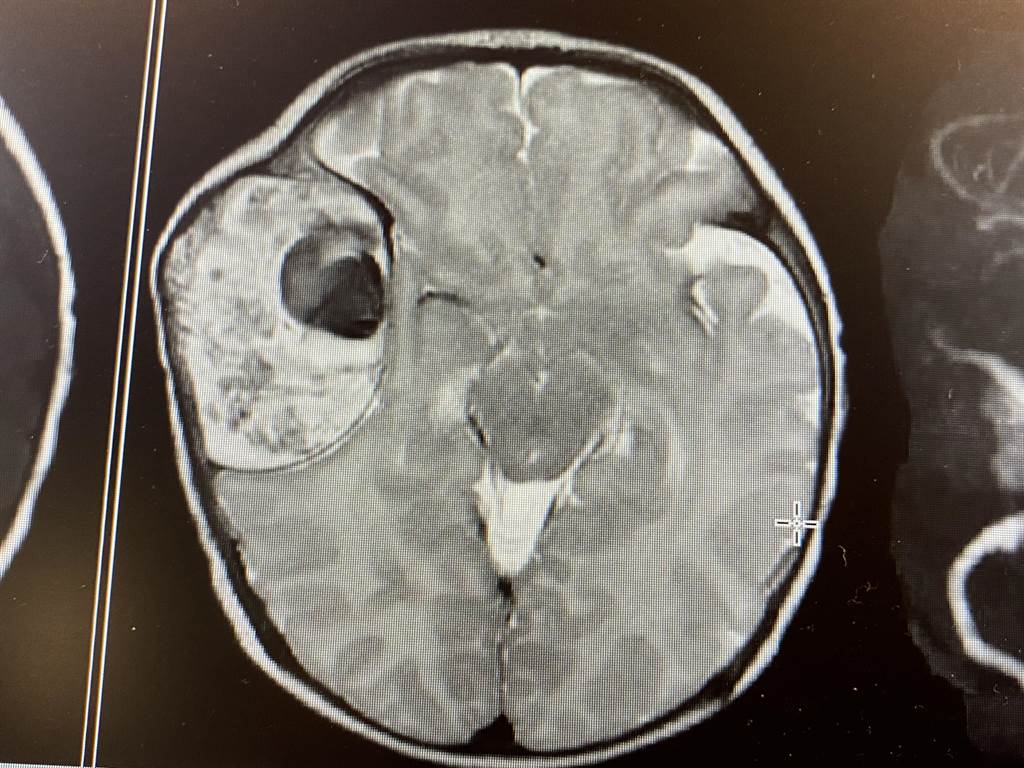

目前已知结节性硬化症为一种基因变异所导致的疾病,临床症状表现非常多样化,并且为进行性,因此,患者从出生前后到成人,需要以病人为中心的全人医疗照护。...